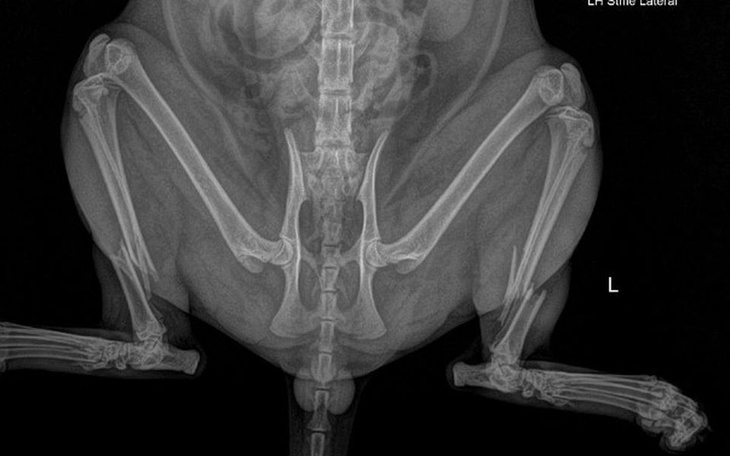

Chcielibyśmy opowiedzieć Wam o historii potrąconego, bezdomnego kotka, którego wszyscy omijali. Pochylił się nad nim Pan Piotr, który sam dokarmia kilka kotów wolno żyjących w Chwałowicach. Pan Piotr zawiózł kotka do przychodni weterynaryjnej, gdzie okazało się, że kot ma złamane obie tylne łapy... Poproszono nas o pomoc, bo kwota ponad 2000,00 zł za operację obu łap to stanowczo za dużo dla karmiciela. Kotek miał połamane obie łapki, przeszedł poważną operację wstawienia tytanowych płytek. Teraz wraca do zdrowia w domku pod opieką Pana Piotra. Opieka nad takim kotkiem to codzienne kontrole, podawanie leków i dbanie o kocie potrzeby, za co jeszcze raz bardzo dziękujemy panu Piotrowi. Na dzień dzisiejszy Kotełek ma mieć wyciągane płytki. Niestety kwota za operację, wizyty kontrolne i leki, wzrosła do 3300 zł. Dlatego zwracamy się do Państwa z ogromną prośbą o wsparcie finansowe, dla Kota Pana Piotra.

Chłopak jest już po zabiegu usunięcia drutu z nóżki, z którym męczył się ponad 8 tygodni, oraz po zabiegu kastracji. Nóżka jest wygojona i chłopak wrócił do pełnej sprawności fizycznej. Została faktura do zapłaty i bezpodstawne groźby poprzedniej właścicielki o chęci odebrania kotka na drodze sądowej.

Otis przesyła pozdrowienia! Chłopak jest już po zabiegu usunięcia drutu z nóżki, z którym męczył się 8 tygodni, oraz po zabiegu kastracji. Z powodu odleżyn jakie zrobiły się pod gipsikiem, Otis jest aktualnie na antybiotyku i dochodzi do siebie w domu tymczasowym pod wspaniałą opieką. W czwartek kolejna kontrola i ściągnięcie szwów. Trzymajcie kciuki za chłopaka!